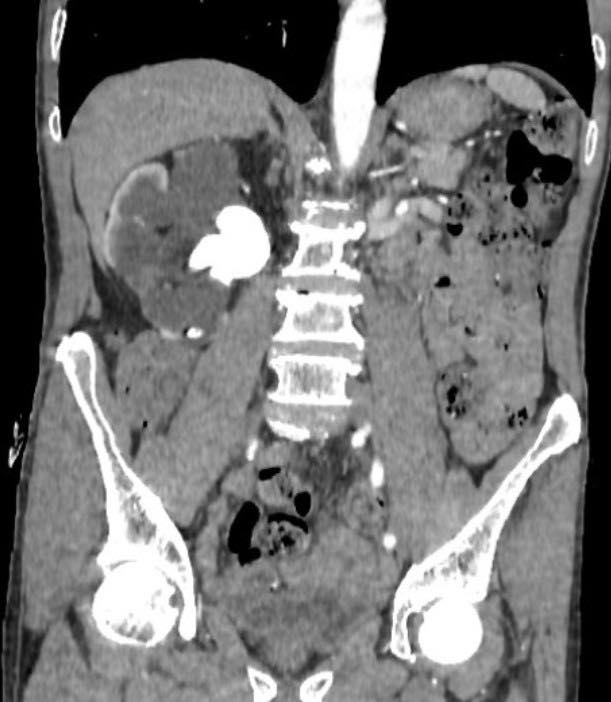

Hình ảnh sỏi thận (ảnh BSCC).

Tuy nhiên, thực tế lại hoàn toàn ngược lại. Rất nhiều bệnh nhân uống thuốc nam ròng rã suốt nhiều năm mà không thăm khám, không theo dõi tiến triển của bệnh. Trong khi đó, sỏi thận âm thầm phát triển, gây tắc nghẽn đường tiết niệu, làm thận giãn dần, suy giảm chức năng mà không gây ra triệu chứng rõ rệt.

Khác với những cơn đau quặn thận dữ dội dễ khiến người bệnh đi khám sớm, nhiều trường hợp sỏi thận diễn tiến lặng lẽ. Khi phát hiện thì thận đã mất chức năng, không còn khả năng hồi phục. Lúc này, giải pháp duy nhất là phẫu thuật cắt bỏ để tránh biến chứng nhiễm trùng, ảnh hưởng đến tính mạng.